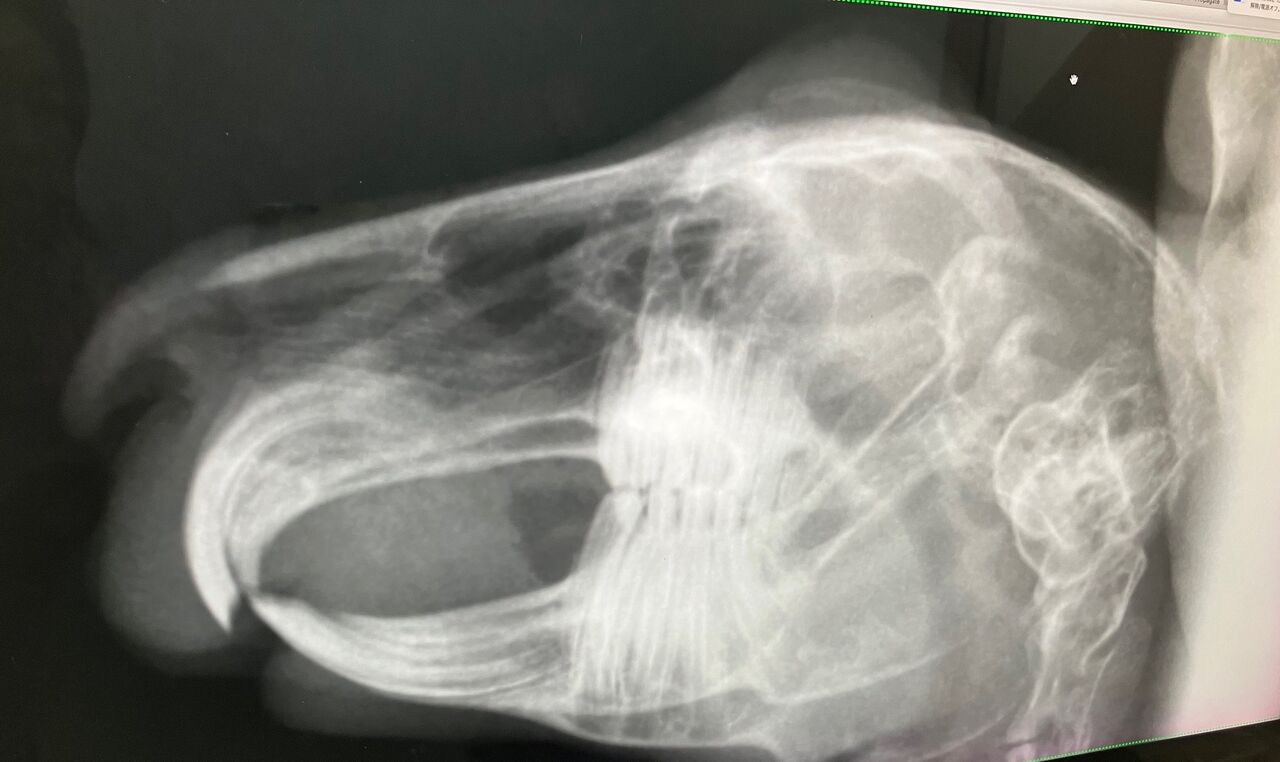

【血液検査とレントゲン】

※クリックで拡大見れます

奥歯(切歯)もキレイ、問題なし。

前歯(切歯)もご覧の通り問題なしっ!